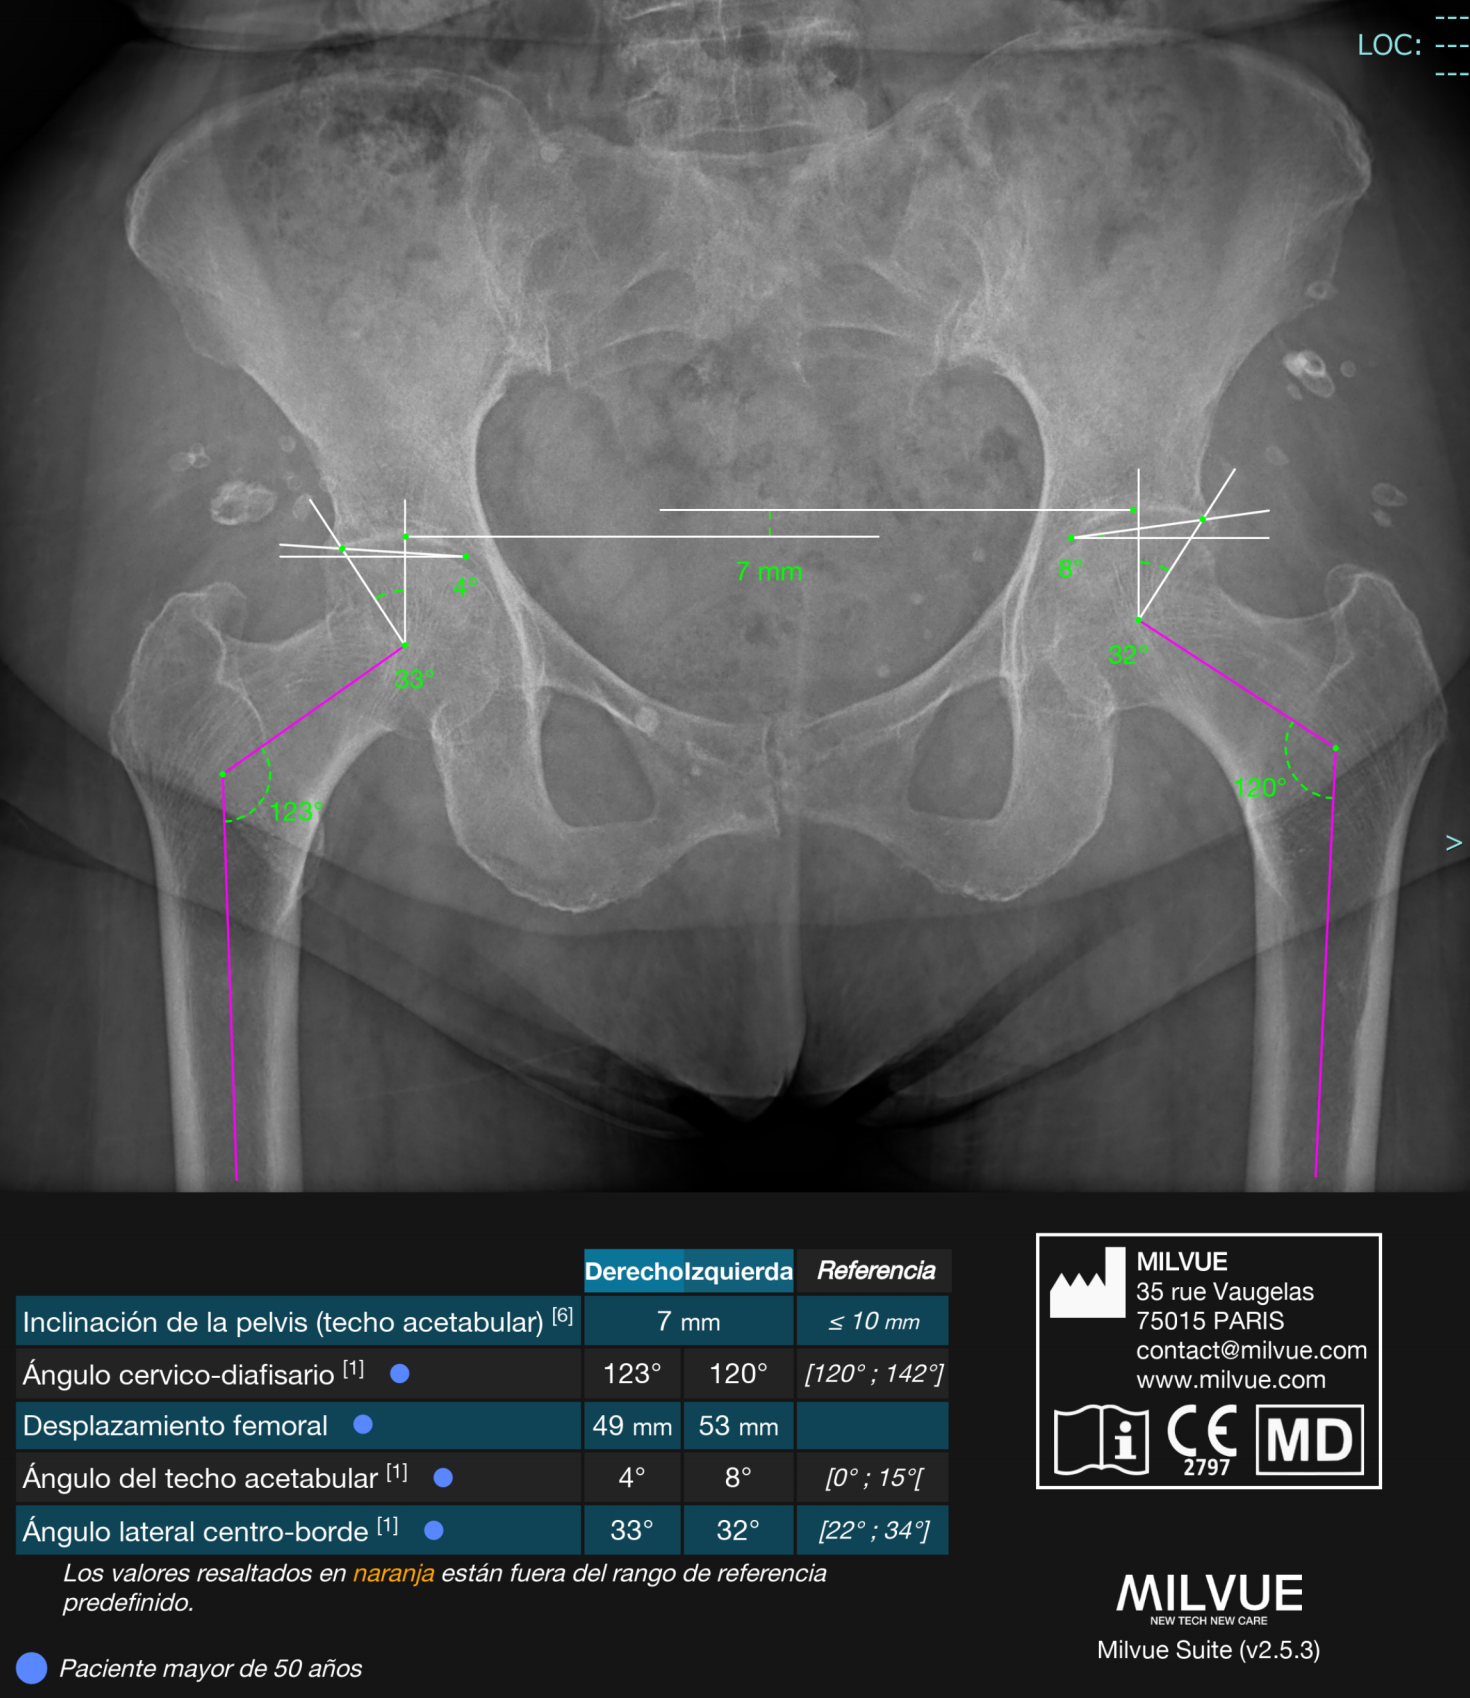

IA para Rayos X – Milvue

Milvue es una solución líder en inteligencia artificial aplicada a Rayos X, especialmente en el área musculoesquelética, con impacto clínico demostrado en servicios de urgencias.

#1 en detección automática de fracturas.

Detección de múltiples patologías en una sola imagen.

Reducción del tiempo de espera hasta en 1 hora.

Incremento del 20–30% en eficiencia diagnóstica.